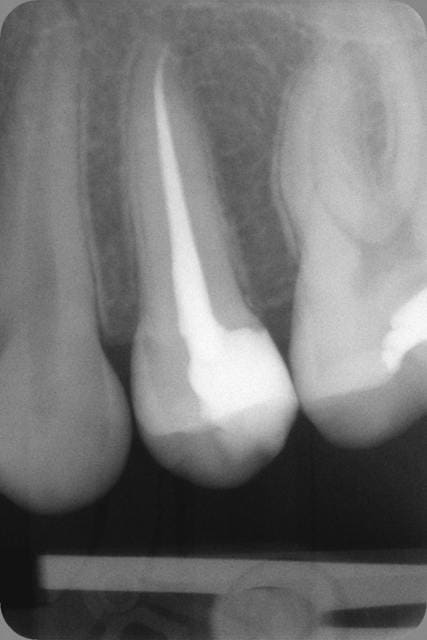

Tiens pour rigoler un peu, je poste une radio pour savoir ce que feraient les uns et les autres sur cette 26 et cette 27.

La réponse des étudiants m'intéresse tout particulièrement.

26 : si la limite est remontable au compo : onlay, sinon cr sur dent vivante

27 : compo

Désolé mais je ne sais pas faire de plan de traitement systématique sur la base d'une seule rx. la 26 peut très vite tourner en endo . souvent on a un bon tiers de tissu carieux supplementaire à ce qui est attendu à la rx.

Je previens le patient que je curette et en fonction de l'etendu des degats on avise mais que plusieurs options seront possibles.

On va dire que techniquement l'onlay est la solution de facilité et que financièrement c'est l'endo ic coiffe c'est pour ca que c'est mieux remboursé non ? pour compenser la difficulté et maigre rémunération de l'endo.)))))

Bon d'après la radio il n'y a pas urgence ca peut être remis à plus tard, c'est que j'ai un de ces planning blindé moi ............)))))))))

Disons 2 amalgames si j'ai de la place.)))))))

Si j'ai pas envie de gagner ma vie, curetage puis biodentine et obturation transitoire type Cvi. Surveillance pour voir la dentine réactionnelle et curetage supplémentaire si nécessaire puis faire l' obturation définitive.

Enfin deux cartouches pour le sanglier dans le superposé et ne pas se merder sur l'axe du canon, car au tarif secu, je viens de mettre la clef sous la porte.

Et pour le volume de la 26, manque de bol pour mon portefeuille, en vrai c'était pas si profond. Je me referai sur la 24 à couronner (bah oui je vais pas laisser un composite 3 faces quand même, cochon de dentiste).

Reste la 7, on verra.